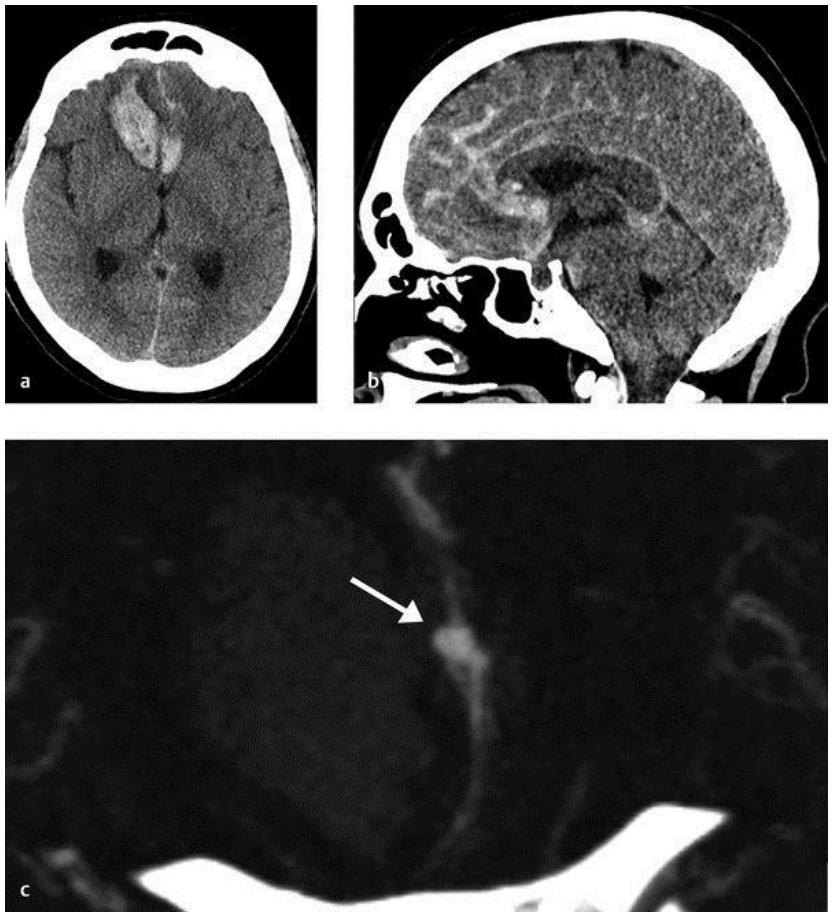

Chụp cắt lớp vi tính (CT) sọ não

CT sọ não không tiêm thuốc cản quang là một kỹ thuật nhanh với độ nhạy rất cao để xác định xuất huyết não cấp tính, và do tính khả dụng cao của nó mà đây được coi như tiêu chuẩn vàng để chẩn đoán xác định xuất huyết não trong các khoa cấp cứu.

CT sọ não ngoài việc chẩn đoán xác định xuất huyết não, còn cung cấp thêm các thông tin hữu ích khác bao gồm vị trí, lan rộng vào não thất, giãn não thất, sự xuất hiện và mức độ phù não, và sự đè đẩy đường giữa cũng như thân não thứ phát do hiệu ứng khối của khối máu. Thể tích khối máu nội sọ là yếu tố dự báo mạnh mẽ đầu ra lâm sàng của bệnh nhân và có thể xác định được nhanh chóng ở khoa cấp cứu dựa vào kỹ thuật đo ABC/2.

Hình ảnh xuất huyết não cấp tính trên CT sọ não thì dễ nhận biết do đặc trưng bởi hình ảnh tăng tỷ trọng so với nhu mô não (trừ khi số lượng máu quá ít). Sự thoái triển của khối máu được đánh dấu bởi sự giảm tỷ trọng dần của khối máu cho tới khi bị dịch hóa hoàn toàn ở giai đoạn mạn tính.

Chụp cắt lớp vi tính mạch não (CT-A)

Đây là kỹ thuật chẩn đoán không xâm lấn hữu ích trong bệnh cảnh xuất huyết não cấp giúp phát hiện các bất thường mạch máu là nguyên nhân của xuất huyết não.

Các yếu tố nên đặt ra nghi ngờ có bất thường mạch não bao gồm: xuất huyết dưới nhện, xuất huyết não ở thùy não, xuất huyết não thất nhiều, tuổi trẻ và không có các yếu tố nguy cơ bệnh lý mạch não (như tăng huyết áp).

Ngoài phát hiện nguyên nhân bất thường mạch máu thì dấu hiệu thoát thuốc cản quang bên trong khối máu trên CT mạch não là một dấu hiệu chỉ điểm dự báo sự lan rộng của khối máu và đầu ra lâm sàng kém cho bệnh nhân. Dấu hiệu thoát thuốc rất có ích giúp định hướng cho phẫu thuật viên trong quá trình phẫu thuật lấy khối máu tụ.

Chụp cộng hưởng từ(MRA) sọ não

Cộng hưởng từ (MRA) có độ nhạy để chẩn đoán xuất huyết não tương đương với CT sọ não không tiêm thuốc cản quang. MRA có thể phát hiện các nguyên nhân gây xuất huyết não như các u não chảy máu hay nhồi máu chuyển dạng chảy máu. Ở các bệnh nhân suy thận hay dị ứng thuốc cản quang thì việc đánh giá mạch não có thể thực hiện được thông qua MRA mạch máu mà không cần tiêm chất tương phản. Tuy nhiên, do giá thành cao, việc thăm khám kéo dài và tính khả dụng thấp hơn CT sọ não nên MRA ít khi được sử dụng để chẩn đoán xuất huyết não trong bệnh cảnh cấp cứu.

Hình ảnh xuất huyết não trên MRA có thể đặt ra nhiều thách thức do biểu hiện của máu thay đổi theo các chuỗi xung, thời gian kể từ lúc bắt đầu chảy máu, kích thước và vị trí chảy máu.